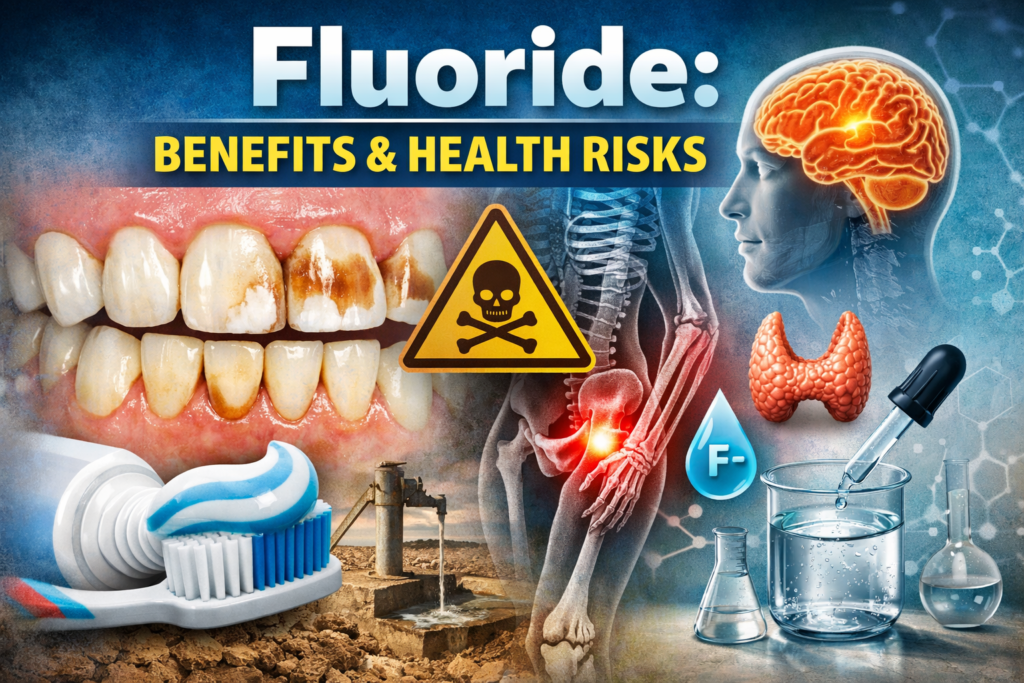

Fluoride can be beneficial in small amounts (mainly for Preventing tooth Decay),But Excess Fluoride Exposure can cause several Health Problems.

- Dental Fluorosis:

This happens when Children Consumes too much Fluoride while Teeth are Developing.

- White streaks or spots on Teeth.

- Brown Stains on Enamel.

- Rough or Pitted Teeth Surface(in Severe Cases)

2. Skeletal Fluorosis:

Long-term Exposure to High Fluoride in Drinking Water (Common in Some Parts of India) can Damage Bones.

3. Neurological Effects:

Some studies Suggest very high Fluoride Exposure may Affect the Brain.

4.Thyroid Problems:

High Fluoride Levels may Interfere with the Thyroid Gland, Especially when iodine intake is low.